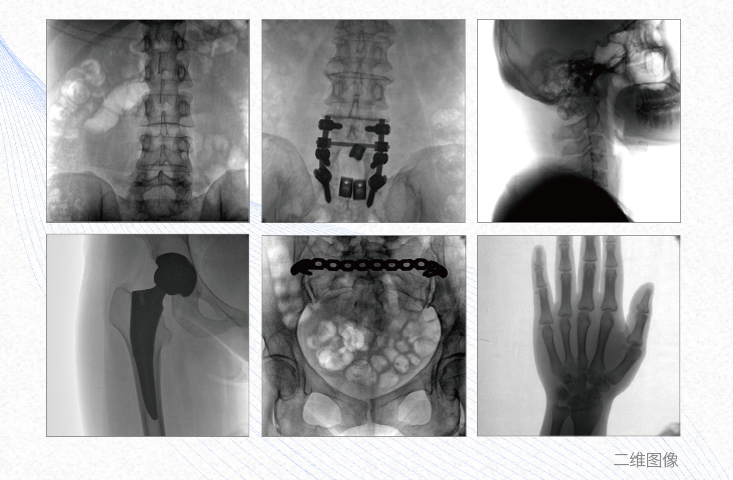

1、脊柱外科

有效重建復(fù)雜的脊柱三維模型,提供準(zhǔn)確的二維、三維圖像,提高螺釘植入的準(zhǔn)確性,縮短手術(shù)時間,減少并發(fā)癥的概率,降低輻射的攝入。

2、創(chuàng)傷外科

例如骨盆骨折內(nèi)固定術(shù),可術(shù)中三維重建髖臼關(guān)節(jié)面,準(zhǔn)確定位并植入螺釘,有效縮短螺釘植入的時間和透視暴露時間,減少術(shù)中及術(shù)后并發(fā)癥發(fā)生的概率。

3、關(guān)節(jié)外科

主要應(yīng)用于肩關(guān)節(jié)、肘關(guān)節(jié)、髖關(guān)節(jié)、膝關(guān)節(jié)的關(guān)節(jié)置換及解剖復(fù)位的定位。它可以準(zhǔn)確地置入假體,減少輻射時間,降低輻射劑量。

4、截骨矯形外科

例如治療先天性脊柱側(cè)后凸畸形,可有效引導(dǎo)術(shù)者植入后路螺釘并切除半錐體,達到滿意的截骨矯正效果。